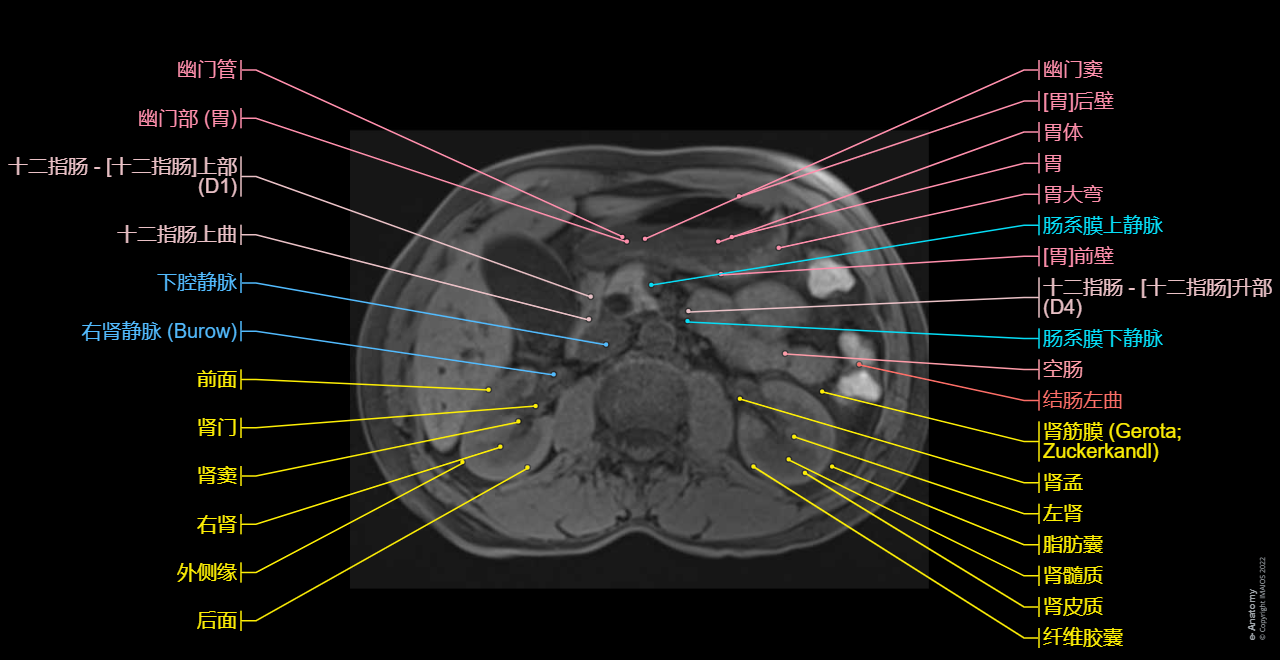

Axial T1 in-phase and axial T1 out-of-phase on the liver: Conventional abdominal MRI imaging to study extraductal structures (hepatic segments, pancreas, spleen, kidneys)